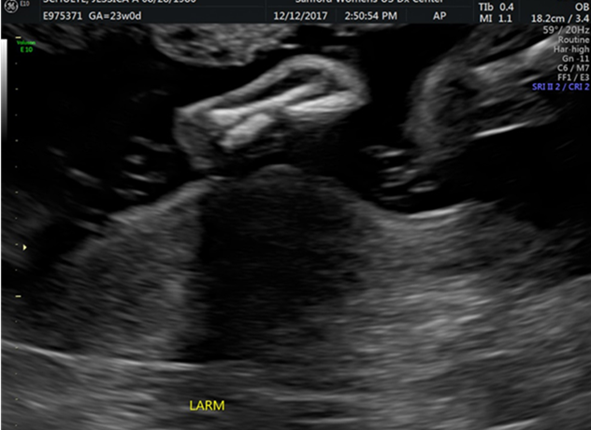

Radial ray defects